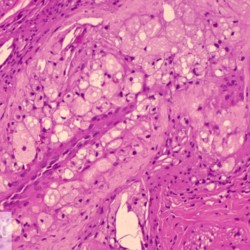

Etiquetes: B-2987/94C 2 total Canine Specie: Canine Organ: Blood vessel Lesion: Atherosclerosis Lesion modifier: - Disease: - Files/Expedient: B-2987/94C Not viewed Canine Specie: Canine Organ: Blood vessel Lesion: Atherosclerosis Lesion modifier: - Disease: - Files/Expedient: B-2987/94C Not viewed Títol Select...Avian (Exotic) (110)Avian (Poultry) (76)Bovine (317)Canine (935)Caprine (47)Equine (257)Feline (326)Ferret (19)General (127)Marine mammal (22)Non-human primate (20)Ovine (328)Porcine (379)Rabbit (61)Reptile (38)Rodent (28)Wildlife (91) Format Select...- (60)Abomasum (37)Adrenal gland (10)Blood (7)Blood vessel (50)Body as a whole (19)Bone (57)Bone marrow (21)Brain (93)Cloaca (1)Diaphragm (2)Ear (5)Esophagus (39)Eye (16)Fetus (12)Gallbladder (23)Gizzard (2)Heart (265)Intestine (356)Joint (32)Kidney (443)Larynx (5)Liver (326)Lung (264)Lymph node (91)Mammary gland (10)Mediastinum (1)Muscle (22)Nasal cavity (22)Nerve (7)Omasum (5)Oral cavity (63)Ovary (14)Oviduct (8)Pancreas (7)Parathyroid (5)Penis (10)Peritoneum (65)Pharynx (9)Pituitary gland (6)Placenta (7)Prostate (8)Proventriculus (3)Reticulum (1)Rumen (28)Sinus (7)Skin (181)Spinal cord (15)Spleen (105)Stomach (125)Teeth (1)Testicle (11)Thoracic cavity (31)Thymus (13)Thyroid gland (5)Tongue (32)Tonsils (11)Trachea (11)Urethra (5)Urinay bladder (61)Uterus (27)Vagina (1)Vulva (1)Yolk sac (1) Cobertura Select...- (152)Abomasitis (26)Abscess (27)Acidosis (1)Adenocarcinoma (20)Adenoma (9)Aerosacculitis (6)Agenesis (1)Agnathia (1)Alopecia (7)Amyloidosis (12)Aneurysm (6)Angiectasis (1)Anthracosis (1)Arteritis (11)Arthritis (15)Arthrogryposis (6)Artifact (4)Ascites (13)Atelectasis (8)Atherosclerosis (5)Atresia (1)Atrial septal defect (2)Atrophy (10)Autolysis (7)Bronchitis (6)Bronchopneumonia (26)Cachexia (2)Carcinoma (103)Cardiomyopathy (19)Cellulitis (2)Chemodectoma (4)Cholangiohepatitis (4)Cholangitis (19)Cholecystitis (4)Cholestasis (5)Chondrodysplasia (2)Chondrosarcoma (2)Chronic passive congestion (13)Chylothorax (2)Cirrhosis (6)Coelomitis (3)Coenurus cerebralis (4)Colitis (40)Congestion (17)Conjunctivitis (5)Coronitis (3)Cryptorchidism (3)Cyst (25)Cystitis (24)Dermatitis (69)Diaphragmatic hernia (4)Dilation (28)Discospondylitis (1)Disseminated intravascular coagulation (7)Dyschondroplasia (1)Dysplasia (29)Ectopia cordis (1)Ectopic ureter (1)Edema (55)Emphysema (5)Encephalitis (5)Endocardiosis (14)Endocarditis (26)Endometritis (5)Enteritis (118)Enterolith (6)Epulis (3)Esophagitis (14)Fasciitis (1)Fibrosis (7)Fibrous osteodystrophy (8)Fistula (1)Folliculitis (3)Fracture (2)Gastritis (34)Gingivitis (5)Glioma (8)Glomerulonephritis (21)Glossitis (25)Glycogenosis (1)Gout (8)Granuloma (2)Granulosa cell tumor (4)Hemangioma (9)Hemangiosarcoma (46)Hematoma (8)Hemoglobinuria (2)Hemopericardium (12)Hemoperitoneum (2)Hemorrhage (100)Hemosiderosis (7)Hemothorax (2)Hepatitis (78)Hernia (11)Histiocytosis (3)Hydatid cyst (11)Hydrocephalus (9)Hydrometra (1)Hydronephrosis (22)Hydropericardium (6)Hydrothorax (3)Hydroureter (5)Hyperkeratosis (8)Hyperostosis (4)Hyperplasia (37)Hypertrophy (9)Hypopigmentation (1)Hypoplasia (7)Hypopyon (1)Impaction (6)Infarction (63)Insulinoma (6)Intussusception (5)Jaundice (17)Laminitis (2)Laryngitis (2)Leiomyoma (5)Leukemia (13)Lipidosis (36)Lipoma (7)Lymphadenitis (45)Lymphadenopathy (7)Lymphangiectasia (6)Lymphangitis (5)Lymphoma (221)Malacia (11)Malignant melanoma (15)Mast cell tumor (11)Mastitis (8)Megaesophagus (2)Melanosis (3)Melena (4)Meningioma (6)Meningitis (6)Meningocele (2)Meningoencephalitis (5)Mesothelioma (5)Methemoglobinemia (2)Mineralization (10)Mucocele (5)Mucometra (1)Multilobular bone tumor (1)Mummification (3)Myelofibrosis (1)Myocarditis (4)Myositis (5)Necrosis (81)Nephritis (113)Nephroblastoma (6)Nephrosclerosis (1)Nephrosis (14)Neuritis (1)Obstruction (13)Omasitis (4)Omphalitis (1)Omphalophlebitis (7)Orchitis (4)Osteoarthrosis (5)Osteomyelitis (9)Otitis (2)Palatoschisis (3)Pancreatitis (3)Panniculitis (3)Papilloma (7)Parakeratosis (14)Patent ductus arteriosus (6)Peliosis hepatis (1)Perforation (17)Pericarditis (35)Peritonitis (39)Persistent right aortic arch (1)Pharyngitis (2)Pheochromocytoma (2)Phlebitis (2)Placentitis (6)Pleuritis (21)Pleuropneumonia (24)Pneumonia (109)Pneumothorax (3)Polycystosis (14)Polyp (5)Polyserositis (6)Posthitis (1)Proctitis (4)Prolapse (3)Prostatitis (3)Proventriculitis (1)Pyelonephritis (24)Pyometra (6)Pyothorax (4)Rhinitis (11)Rumenitis (6)Rupture (24)Salpingitis (3)Sarcoma (57)Sclerosis (1)Scoliosis (2)Seminoma (2)Sequestrum (2)Serous atrophy (14)Sinusitis (7)Splenitis (14)Splenomegaly (9)Spondylitis (6)Spondylosis (1)Stenosis (9)Stomatitis (32)Tenosynovitis (2)Teratoma (3)Thricobezoar (2)Thrombosis (16)Tonsilitis (4)Torsion (13)Tracheitis (4)Tympany (7)Typhlitis (8)Typhlocolitis (4)Ulcer (43)Urethritis (1)Urolithiasis (36)Uroperitoneum (1)Uveitis (1)Vasculitis (15)Ventricular septal defect (3)Volvulus (11) Matèria Select... - (14)- (1653)- (152)Abomasitis - Catarrhal (2)Abomasitis - Catarrhal-hemorrhagic (1)Abomasitis - Chronic (1)Abomasitis - Fibrinous-necrotizing (2)Abomasitis - Hyperplasic (5)Abomasitis - Hyperplasic - Chronic (1)Abomasitis - Necrotic (1)Abomasitis - Necrotizing (2)Abomasitis - Ulcerative (5)Adenocarcinoma (9)Aerosacculitis - Granulomatous (1)Amyloidosis - Chronic (1)Arteritis - Necrotic (2)Arteritis - Necrotizing (1)Arthritis - Chronic (4)Arthritis - Fibrinous-purulent (3)Arthritis - Serous (4)Arthritis - Subacute (1)Ascites - Serous (1)Atrophy - Serous (1)Bronchitis - Catarrhal (3)Bronchitis - Suppurative (1)Bronchopneumonia - Catarrhal-purulent (17)Bronchopneumonia - Fibrinous (1)Bronchopneumonia - Granulomatous (1)Bronchopneumonia - Purulent (1)Bronchopneumonia - Suppurative (5)Carcinoma - Adenocarcinoma (33)Carcinoma - Adenocarcinoma - Hepatocellular (2)Carcinoma - Adenocarcinoma - Mucinous (1)Carcinoma - Basosquamous (1)Carcinoma - Cholangiocellular (3)Carcinoma - Hepatocellular (4)Carcinoma - Metastatic (3)Carcinoma - Squamous cell carcinoma (13)Carcinoma - Transitional cell (2)Cardiomyopathy - Dilated (13)Cardiomyopathy - Hypertrophic (6)Cellulitis - Necrotizing (1)Cholangitis - Chronic (8)Cholangitis - Hyperplasic (3)Cholecystitis - Fibrinous-necrotizing (1)Coelomitis - Fibrinous (1)Coelomitis - Granulomatous (1)Colitis - Catarrhal (3)Colitis - Catarrhal-hemorrhagic (1)Colitis - Fibrinous (1)Colitis - Fibrinous-necrotizing (1)Colitis - Fibrinous-necrotizing (Diphtheritic) (6)Colitis - Granulomatous (2)Colitis - Hemorrhagic (4)Colitis - Hemorrhagic-necrotizing (3)Colitis - Necrotizing (2)Colitis - Ulcerative (6)Congestion - Chronic (2)Conjunctivitis - Hyperplasic (1)Conjunctivitis - Purulent (3)Coronitis - Ulcerative (1)Cystitis - Chronic (3)Cystitis - Fibrinous (1)Cystitis - Fibrinous-necrotizing (1)Cystitis - Follicular (1)Cystitis - Hemorrhagic (6)Cystitis - Hemorrhagic-ulcerative (1)Cystitis - Necrotizing (9)Cystitis - Perforated (1)Dermatitis - Granulomatous (14)Dermatitis - Hyperkeratotic (10)Dermatitis - Hyperplasic (proliferative) (1)Dermatitis - Hyperplastic (10)Dermatitis - Necrotizing (4)Dermatitis - Pustular (4)Dermatitis - Ulcerative (2)Dilation - Chronic (1)Discospondylitis - Necrotizing (1)Dysplasia - Follicular (5)Edema - Interstitial (6)Emphysema - Interstitial (1)Encephalitis - Granulomatous (1)Encephalitis - Nonsuppurative (1)Endocardiosis - Mitral (7)Endocardiosis - Mitral - Chronic (5)Endocarditis - Valvular (6)Endocarditis - Valvular - Mitral (7)Endocarditis - Valvular - Pulmonic (1)Endocarditis - Valvular - Subacute (1)Endocarditis - Valvular - Subaortic (5)Endocarditis - Valvular - Tricuspid (4)Endometritis - Purulent (3)Endometritis - Purulent-hemorrhagic (2)Enteritis - Catarrhal (23)Enteritis - Catarrhal - Acute (1)Enteritis - Catarrhal-hemorrhagic (5)Enteritis - Catarrhal-hemorrhagic - Acute (2)Enteritis - Fibrinous (16)Enteritis - Fibrinous - Acute (3)Enteritis - Fibrinous-necrotizing (7)Enteritis - Granulomatous (14)Enteritis - Granulomatous - Chronic (1)Enteritis - Granulomatous - Multifocal (1)Enteritis - Hemorrhagic (17)Enteritis - Hemorrhagic - Acute (1)Enteritis - Hemorrhagic-necrotizing (1)Enteritis - Hyperplasic (proliferative) (4)Enteritis - Necrotizing (4)Enteritis - Necrotizing - Acute (1)Enteritis - Necrotizing - Hemorrhagic (1)Enteritis - Necrotizing-ulcerative (2)Enteritis - Ulcerative (1)Enteritis - Ulcerative-hemorrhagic (1)Esophagitis - Erosive-ulcerative (6)Esophagitis - Necrotizing (4)Esophagitis - Ulcerative (1)Esophagitis - Ulcerative-necrotizing (1)Fasciitis - Fibrinous-purulent (1)Folliculitis - Purulent (2)Gastritis - Catarrhal (2)Gastritis - Chronic (1)Gastritis - Follicular (1)Gastritis - Hemorrhagic (2)Gastritis - Hemorrhagic-necrotizing (1)Gastritis - Hypertrophic (2)Gastritis - Inclusion bodies (1)Gastritis - Mineralization (1)Gastritis - Mycotic (1)Gastritis - Necrotizing (2)Gastritis - Ulcerative (6)Gastritis - Uremic (3)Gingivitis - Erosive (2)Gingivitis - Hyperplasic (proliferative) (1)Gingivitis - Necrotizing (1)Glomerulonephritis - Chronic (7)Glomerulonephritis - Membranoproliferative (3)Glomerulonephritis - Membranoproliferative - Chronic (1)Glomerulonephritis - Membranous (3)Glomerulonephritis - Membranous - Chronic (1)Glomerulonephritis - Proliferative (2)Glomerulonephritis - Subacute (1)Glossitis - Erosive (2)Glossitis - Granulomatous (6)Glossitis - Hyperplasic (1)Glossitis - Hyperplasic (proliferative) (2)Glossitis - Hyperplastic (1)Glossitis - Necrotizing (2)Glossitis - Necrotizing - Focal (1)Glossitis - Ulcerative (6)Glossitis - Ulcerative - Multifocal (1)Glossitis - Ulcerative - Subacute (1)Glycogenosis (1)Granuloma - Eosinophilic (1)Hemangiosarcoma - Metastatic (2)Hemorrhage - Acute (1)Hemorrhage - Subcapsular (3)Hepatitis - Abscess (9)Hepatitis - Acute (3)Hepatitis - Chronic (4)Hepatitis - Chronic interstitial (6)Hepatitis - Granulomatous (7)Hepatitis - Interstitial - Multifocal (1)Hepatitis - Interstitial - Subacute (1)Hepatitis - Necrotizing (17)Hepatitis - Necrotizing - Acute (2)Hepatitis - Necrotizing - Hemorrhagic (1)Hepatitis - Necrotizing - Subacute (1)Hepatitis - Pyogranulomatous (7)Hepatitis - Subacute (4)Hydronephrosis - Chronic (1)Hydropericardium - Chronic (1)Hyperplasia - Erythroid (1)Hyperplasia - Lymphoid (3)Hyperplasia - Myeloid (1)Hyperplasia - Nodular (8)Hypertrophy - Concentric (2)Hypertrophy - Eccentric (3)Infarction - Acute (17)Infarction - Acute - Multifocal (2)Infarction - Chronic (5)Infarction - Chronic - Multifocal (1)Infarction - Subacute (18)Infarction - Subacute - Focal (2)Laminitis - Chronic (2)Laryngitis - Necrotic (1)Laryngitis - Necrotizing (1)Leukemia - Lymphoid leukemia (2)Leukemia - Non-lymphoid leukemia (6)Lipidosis - Multifocal (1)Lipidosis - Panlobular (1)Lipidosis - Panlobular - Generalized (2)Lymphadenitis - Granulomatous (24)Lymphadenitis - Granulomatous - Chronic (3)Lymphadenitis - Hemorrhagic (1)Lymphadenitis - Necrotizing (5)Lymphadenitis - Necrotizing (caseous) (11)Lymphangitis - Granulomatous (1)Lymphangitis - Purulent (1)Lymphangitis - Ulcerative (1)Lymphoma - Alimentary lymphoma (7)Lymphoma - Cutaneous lymphoma (6)Lymphoma - Lymphosarcoma (2)Lymphoma - Mediastinal lymphoma (1)Lymphoma - Multicentric lymphoma (29)Malignant melanoma - Malignant (1)Malignant melanoma - Metastatic (1)Mast cell tumor - Metastatic (1)Mastitis - Fibrinous-purulent (2)Mastitis - Necrotic (1)Mastitis - Purulent (3)Mastitis - Suppurative (1)Meningitis - Fibrinous-purulent (2)Meningitis - Purulent (4)Meningoencephalitis - Necrotizing (3)Meningoencephalitis - Nonsuppurative (2)Mineralization - Metastatic (4)Myocarditis - Fibrous - Chronic (1)Myocarditis - Granulomatous (1)Myositis - Purulent (2)Necrosis - Acute (1)Necrosis - Cortical (5)Necrosis - Follicular (1)Necrosis - Papillary (8)Necrosis - Papillary - Acute (3)Necrosis - Subacute (3)Necrosis - Tubular (6)Nephritis - Embolic (2)Nephritis - Embolic suppurative (7)Nephritis - Granulomatous (27)Nephritis - Granulomatous - Chronic (1)Nephritis - Granulomatous - Multifocal (1)Nephritis - Interstitial (6)Nephritis - Interstitial - Acute (4)Nephritis - Interstitial - Chronic (41)Nephritis - Interstitial - Subacute (12)Nephritis - Purulent (7)Nephritis - Purulent - Acute (2)Nephritis - Purulent - Multifocal (3)Nephrosis - Cholemic (3)Nephrosis - Hemoglobinuric (10)Omasitis - Fibrinous-necrotizing (1)Omasitis - Hyperkeratotic (1)Omasitis - Necrotizing (2)Omphalophlebitis - Fibrinous-purulent (2)Omphalophlebitis - Purulent (3)Orchitis - Necrotizing (1)Osteomyelitis - Necrotizing (7)Osteomyelitis - Purulent (2)Otitis - Necrotizing (1)Otitis - Proliferative (1)Pancreatitis - Acute (1)Pancreatitis - Chronic (1)Pancreatitis - Granulomatous (1)Panniculitis - Fibrinous-purulent (1)Panniculitis - Necrotic (1)Panniculitis - Parasitic (1)Perforation - Acute (2)Pericarditis - Fibrinous (19)Pericarditis - Fibrinous - Subacute (1)Pericarditis - Fibrinous-necrotizing (1)Pericarditis - Fibrinous-purulent (3)Pericarditis - Fibrous (1)Pericarditis - Fibrous - Chronic (1)Pericarditis - Gangrenous (6)Pericarditis - Granulomatous (1)Pericarditis - Granulomatous - Chronic (2)Peritonitis - Acute (1)Peritonitis - Fibrinous (11)Peritonitis - Fibrinous - Subacute (1)Peritonitis - Fibrinous-purulent (5)Peritonitis - Fibrous (3)Peritonitis - Granulomatous (6)Peritonitis - Purulent (1)Peritonitis - Purulent-hemorrhagic (1)Peritonitis - Pyogranulomatous (3)Pharyngitis - Fibrinous-necrotizing (1)Pharyngitis - Ulcerative (1)Pheochromocytoma - Metastatic (1)Phlebitis - Purulent (1)Placentitis - Fibrinous-necrotizing (1)Placentitis - Necrotic (1)Placentitis - Necrotizing (1)Pleuritis - Chronic (1)Pleuritis - Fibrinous (3)Pleuritis - Fibrinous-purulent (2)Pleuritis - Fibrous (2)Pleuritis - Granulomatous (3)Pleuritis - Hyperplastic (2)Pleuritis - Purulent (2)Pleuritis - Pyogranulomatous (1)Pleuropneumonia - Fibrinous (13)Pleuropneumonia - Fibrinous-necrotizing (5)Pleuropneumonia - Granulomatous (2)Pleuropneumonia - Hemorrhagic-necrotizing (4)Pneumonia - Aspiration (11)Pneumonia - Bronchointerstitial (4)Pneumonia - Bronchointerstitial - Subacute (1)Pneumonia - Embolic (5)Pneumonia - Granulomatous (37)Pneumonia - Granulomatous - Multifocal (4)Pneumonia - Hemorrhagic-necrotizing (2)Pneumonia - Interstitial (7)Pneumonia - Interstitial - Acute (8)Pneumonia - Interstitial - Chronic (6)Pneumonia - Interstitial - Subacute (15)Pneumonia - Necrotizing (2)Pneumonia - Pyogranulomatous (2)Pneumonia - Verminous (5)Polyserositis - Fibrinous (6)Polyserositis - Fibrous (1)Proctitis - Fibrinous-necrotizing (1)Proctitis - Parasitic (2)Prostatitis - Purulent (1)Pyelonephritis - Acute (2)Pyelonephritis - Chronic (3)Rhinitis - Catarrhal (2)Rhinitis - Fibrinous (1)Rhinitis - Granulomatous (4)Rhinitis - Purulent (3)Rumenitis - Acute (1)Rumenitis - Erosive (1)Rumenitis - Necrotizing (1)Rupture - Acute (3)Sarcoma - Fibrosarcoma (12)Sarcoma - Hemangiosarcoma (11)Sarcoma - Histiocytic (7)Sarcoma - Metastatic (1)Sarcoma - Multilobular tumor of bone (1)Sequestrum - Chronic (2)Sinusitis - Suppurative (1)Splenitis - Granulomatous (8)Splenitis - Granulomatous - Chronic (1)Splenitis - Necrotizing (3)Splenitis - Necrotizing (caseous) (2)Spondylitis - Necrotizing (2)Stenosis - Intestinal (1)Stenosis - Valvular - Subaortic (4)Stomatitis - Erosive (12)Stomatitis - Erosive-ulcerative (3)Stomatitis - Fibrinous-necrotizing (1)Stomatitis - Fibrinous-necrotizing (Diphtheritic) (1)Stomatitis - Granulomatous (1)Stomatitis - Hyperplasic (1)Stomatitis - Hyperplasic (proliferative) (1)Stomatitis - Necrotizing (2)Stomatitis - Ulcerative (5)Stomatitis - Ulcerative - Multifocal (1)Stomatitis - Ulcerative-necrotizing (1)Tonsilitis - Necrotizing (4)Torsion - Acute passive hyperemia (5)Tracheitis - Catarrhal (3)Tracheitis - Fibrinous (1)Tracheitis - Granulomatous (1)Typhlitis - Catarrhal (1)Typhlitis - Fibrinous-necrotizing (2)Typhlitis - Hemorrhagic (2)Typhlitis - Ulcerative-hemorrhagic (1)Typhlocolitis - Fibrinous-necrotizing (2)Typhlocolitis - Proliferative (1)Ulcer - Chronic (6)Ulcer - Multifocal (2)Ulcer - Mycotic (1)Ulcer - Perforated (6)Urethritis - Hemorrhagic (1)Urolithiasis - Chronic (2)Uveitis - Granulomatous (1)Vasculitis - Granulomatous (1)Vasculitis - Necrotizing (1) Editor Select...- (1970)Acidosis (2)Actinobacillosis (Pleuropneumonia) (11)Aelurostrongylosis (2)African horse sickness (13)African swine fever (14)Alopecia X (1)Anaplasmosis (4)Anthrax (2)Aortic thromboembolism (feline) (7)Ascariasis (15)Aspergillosis (18)Atopic dermatitis (1)Atrophic rhinitis (3)Babesiosis (6)Blackhead (1)Bluetongue (11)Border disease (2)Bovine viral diarrhea (21)Brucellosis (2)Candidiasis (5)Canine distemper (14)Caprine arthritis-encephalitis (2)Capture myopathy (1)Cardiac insufficiency (17)Caseous lymphadenitis (7)Chlamydiosis (2)Classical swine fever (19)Clostridiosis (19)Coccidiosis (9)Coenurosis (4)Colibacillosis (21)Contagious ecthyma (7)Copper toxicosis (11)Cowdriosis (Heartwater) (3)Cryptococcosis (3)Cryptosporidiosis (2)Cysticercosis (23)Demodicosis (1)Diabetes (1)Dicrocoeliosis (5)Dictyocaulosis (4)Dirofilariasis (7)Discoid lupus erythematosus (3)Echinococcosis (17)Edema disease (7)Egg drop syndrome (1)Encephalitozoonosis (5)Enterotoxemia (1)Enzootic bovine leukosis (46)Epitheliogenesis imperfecta (3)Equine rhinopneumonitis (2)Equine verminous arteritis (strongylosis) (7)Erysipelas (5)Exudative epidermitis (7)Fasciolasis (11)Feline eosinophilic dermatoses (1)Feline hepatic lipidosis (8)Feline histiocytosis (4)Feline infectious peritonitis (38)Feline leukemia (4)Feline lower urinary tract disease (3)Feline panleukopenia (16)Feline viral rhinotracheitis (1)Flea allergy dermatitis (1)Foot and mouth disease (2)Gasterophilosis (4)Glasser's disease (15)Gousiekte (4)Gout (6)Haemonchosis (9)Hemolytic anemia (4)Hemorrhagic diathesis (1)Hepatic insufficiency (11)Hepatosis dietetica (7)Herpesvirosis (6)Hyperadrenocorticism (7)Hyperparathyroidism (10)Hypertrophic osteopathy (6)Hypervitaminosis D (1)Hypodermosis (1)Inclusion body hepatitis (4)Infectious bovine rhinotracheitis (5)Infectious bronchitis (5)Infectious canine hepatitis (13)Influenza (4)Juvenile nephropathy (8)Lamb dysentery (4)Leishmaniasis (28)Leptospirosis (1)Leukosis (5)Listeriosis (4)Lumpy skin disease (3)Maedi-visna (4)Malignant catarrhal fever (12)Mange (6)Mannheimiosis (5)Marek's disease (7)Metabolic bone disease (2)Mucoid enteropathy (5)Mulberry heart disease (5)Myasis (1)Mycobacteriosis (22)Mycosis fungoides (6)Myxomatosis (3)Necrobacillosis (5)Neonatal isoerythrolysis (6)Nocardiosis (4)Oestrosis (2)Onchocerciasis (1)Osteochondrosis (1)Ostertagiosis (6)Ovine pulmonary adenocarcinoma (5)Oxyuriasis (1)Pacheco's disease (4)Papillomatosis (6)Paratuberculosis (18)Parvovirosis (17)Pasteurellosis (11)Pemphigus foliaceus (1)Periodontal disease (1)Polioencephalomalacia of ruminants (4)Polyarteritis nodosa (3)Polycystic kidney disease (13)Porcine circovirosis (11)Porcine dermatitis and nephropathy syndrome (9)Porcine proliferative enteropathy (4)Porcine reproductive and respiratory syndrome (6)Porcine stress syndrome (1)Pox (13)Pregnancy toxemia (3)Proventricular dilatation disease (2)Pseudotuberculosis (yersiniosis) (2)Psittacine beak and feather disease (PBFD) (5)Pyoderma (4)Q fever (4)Rabbit hemorrhagic disease (2)Renal insufficiency (12)Reticuloendotheliosis (2)Rhodococcosis (1)Rickets (1)Rinderpest (2)Salmonellosis (34)Sarcosporidiosis (2)Schmallenberg (7)Septicemia (23)Spirocercosis (11)Streptococcosis (5)Strongylosis (1)Swine dysentery (5)Systemic coronavirosis (5)Tetralogy of Fallot (5)Theileriosis (13)Thromboembolism (5)Toxoplasmosis (11)Transmissible viral proventriculitis (1)Traumatic reticuloperitonitis (3)Traumatism (16)Tuberculosis (58)Ulcerative lymphangitis (1)Uremic syndrome (20)Viral arthritis (6)White muscle disease (9)Wobbler syndrome (2)Xanthomatosis (1)Zygomycosis (4) Idioma Select...- (1180)Bacterial (501)Degeneration (106)Fungal (46)Hemodynamic (112)Idiopathic (22)Inflammation (58)Malformation (88)Neoplasia (343)Nutritional (41)Parasitic (243)Physical/Chemical (93)Toxic (44)Viral (304) Ítem destacat Porcine Sow. Porcine Ulcerative Dermatitis Syndrome (PUDS). Interface dermatitis. Lesions were neither painful nor pruritic. University of Pretoria, South…